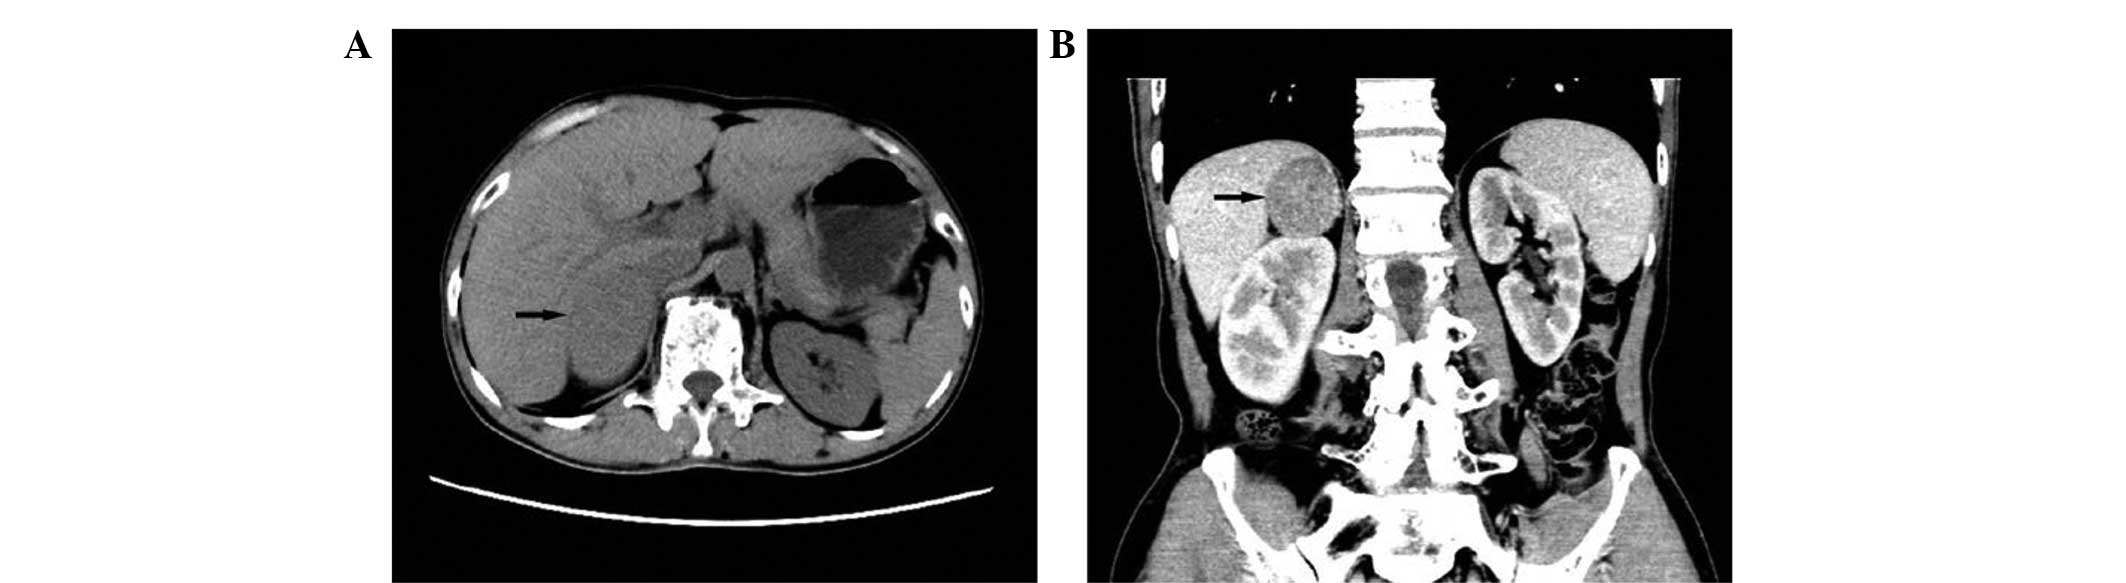

Adrenal sarcomatoid carcinoma is a rare adrenal carcinoma. To the best of our knowledge, only 11 cases have been reported since 1987. Adrenal sarcomatoid carcinoma presents a diagnostic challenge due to its atypical symptoms and histological patterns. At the time of diagnosis, a large percentage of patients are already at the metastatic stage and succumb within a few months. The present study reports a case of a 59‑year‑old man presenting with asthenia and weight loss with adrenal sarcomatoid carcinoma metastatic to the lung. A computed tomography (CT) scan and ultrasonography of the patient's abdomen suggested a large homogeneous mass in the right adrenal gland, and a CT scan of his chest suggested lung metastasis. Right adrenalectomy was performed. Histological examination revealed that the tumor was composed of sarcomatous and carcinomatous differentiation elements. Immunohistochemical examination revealed tumor cell positivity for vimentin and cytokeratin. At the 6‑month follow‑up the patient exhibited no disease progression and refused further proposed treatment. The patient was alive at the time of writing the current report. The present case report additionally reviews the literature, for the purpose of raising awareness of these rare lesions and assisting in achieving accurate diagnoses and effective treatment.